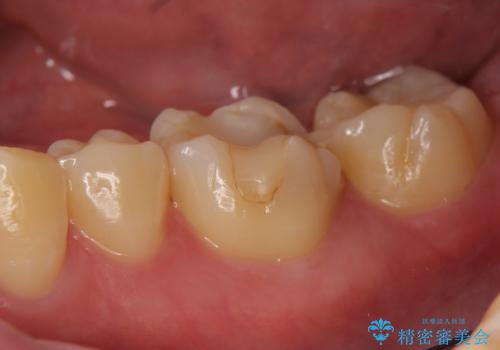

セラミックインレー しみる歯の治療